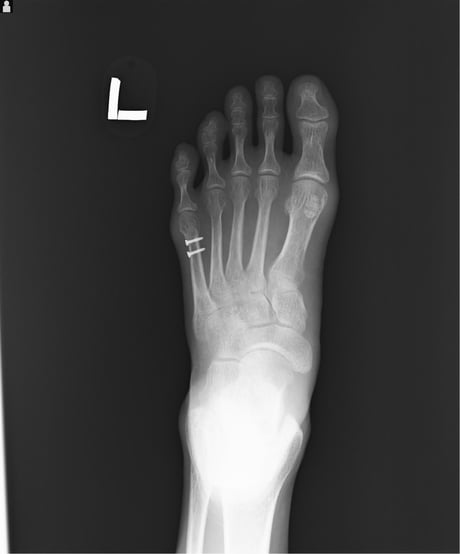

〇第五中足骨骨折

内科で貧血を起こし転倒 安静後立ち上がることができたので帰宅

翌日痛みを訴え来院されました。明らかに骨折の疑いがあるのっで

レントゲン検査を依頼し骨折を確認しました。

病院では通常長靴のようなギプスを巻き、週ごとに骨の状態をレントゲン検査して経過観察していきますが、高齢で足元も不安定なので簡単な副子(あてがう物)と包帯で固定しました。

毎日来院してもらい患部を清潔にし超音波と軽擦(軽くマッサージをして浮腫をとる)をしました。経過良好です。

○第5中足骨骨折

足首をねんざした時に同時に起きる骨折です。

昔から「げた骨折」と呼ばれたもので、当時は下駄のひもが切れた時足の外側が地面に叩き付けられたために骨折したからでしょうか・・?今でも「げた」言えばこの骨折意味します。 整骨院でもよく扱う骨折です。

通常整形外科では足の指先から膝下までのギプスをまき足底にヒールと呼ぶゴムパットをつけます。

ただこのギプスは外も家の中も常にブーツを履いた様なもので、しかもヒールが片方だけにあるので

非常に歩きにくいものです。簡単に言えば片足に10センチのヒールのあるブーツ、片方は裸足といった具合です。

また一ヶ月ほど固定するので夏などは想像したくありません。私も整形外科勤務時はこのギプスを患者さんに巻いていましたが、取り外すときは息を止めてギプスカッターを使用していました。(くさ~)

当院ではブーツの様なギプスは巻かず、副子を外からかぶせ包帯で固定します。

毎日固定は外し患部の清拭、浮腫の除去、動かせる関節は早期からリハビリ。これにより患者さんは気持ちよく過ごすことができます。固定期間からリハビリを開始するので関節の拘縮も防ぎ早期回復につながります。

○ アスリートの骨折 ラクビー部

日々ハードな練習と試合をこなしている学生の症例です。

今回は足関節を捻挫して来院しましたが、腫脹(はれ)が強くレントゲン検査を依頼しました。

足首の捻挫に伴う骨折は認められませんでしたが、過去に何か所も骨折をしていたことが判明しました。

親指の種子骨と言われる石ころの様な骨が割れています。第3中足骨が骨折しています。くるぶしの外側の

外果(がいか)に小さな骨の破片があり、やはり骨折です。

スポーツの現場では休むことができません。一般人であればギプスをして一ヶ月休めばよいのですが、短い学生生活の中でシーズンもやはり短いものです。この症例の様にギプスも何もしないで痛みが取れてしまう骨折もあります。

限られた時期に選手の意向をよく把握して過剰な処置ひかえて、できる限り早期に運動ができるように心がけています。

ギプスをして「休んでください」と言うのは簡単ですが、学生選手には引退を宣言させるのと同じです。

限られた学生生活で後悔しないよう最大限の工夫を常に考えています。